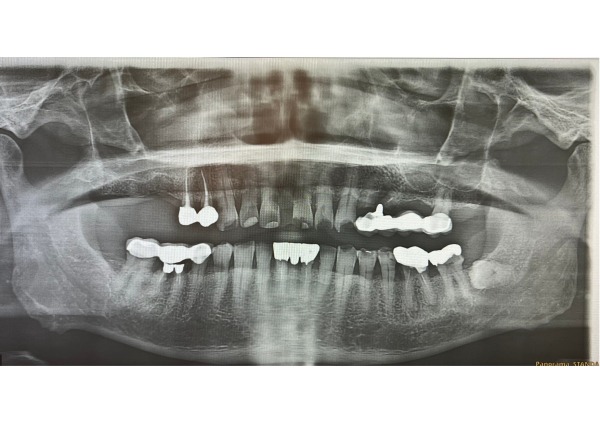

エックス線写真を撮影したところ、左上のブリッジの下に虫歯が広がり、被せ物が揺れていました。虫歯が非常に大きく、もう一度同じブリッジで治療することができないため、右上と同じ部分入れ歯を希望されました。